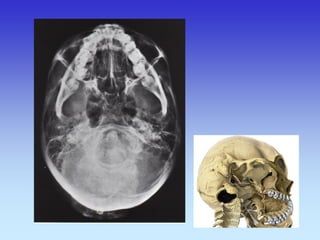

KOSTI GLAVE

Kosti lubanje – rtg.

PROFILNA SNIMKA GLAVE

LUBANJA Baza 1. Parijetalna kost 2. Lambdoidna sutura 3. Foramen magnum 4. Petrozni dio temporalne kosti 5. Mandibula 6. Mastoidne stanice